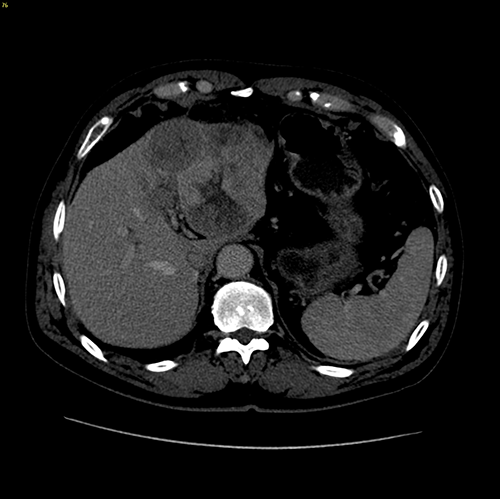

左肝癌、门静脉癌栓---左半肝切除